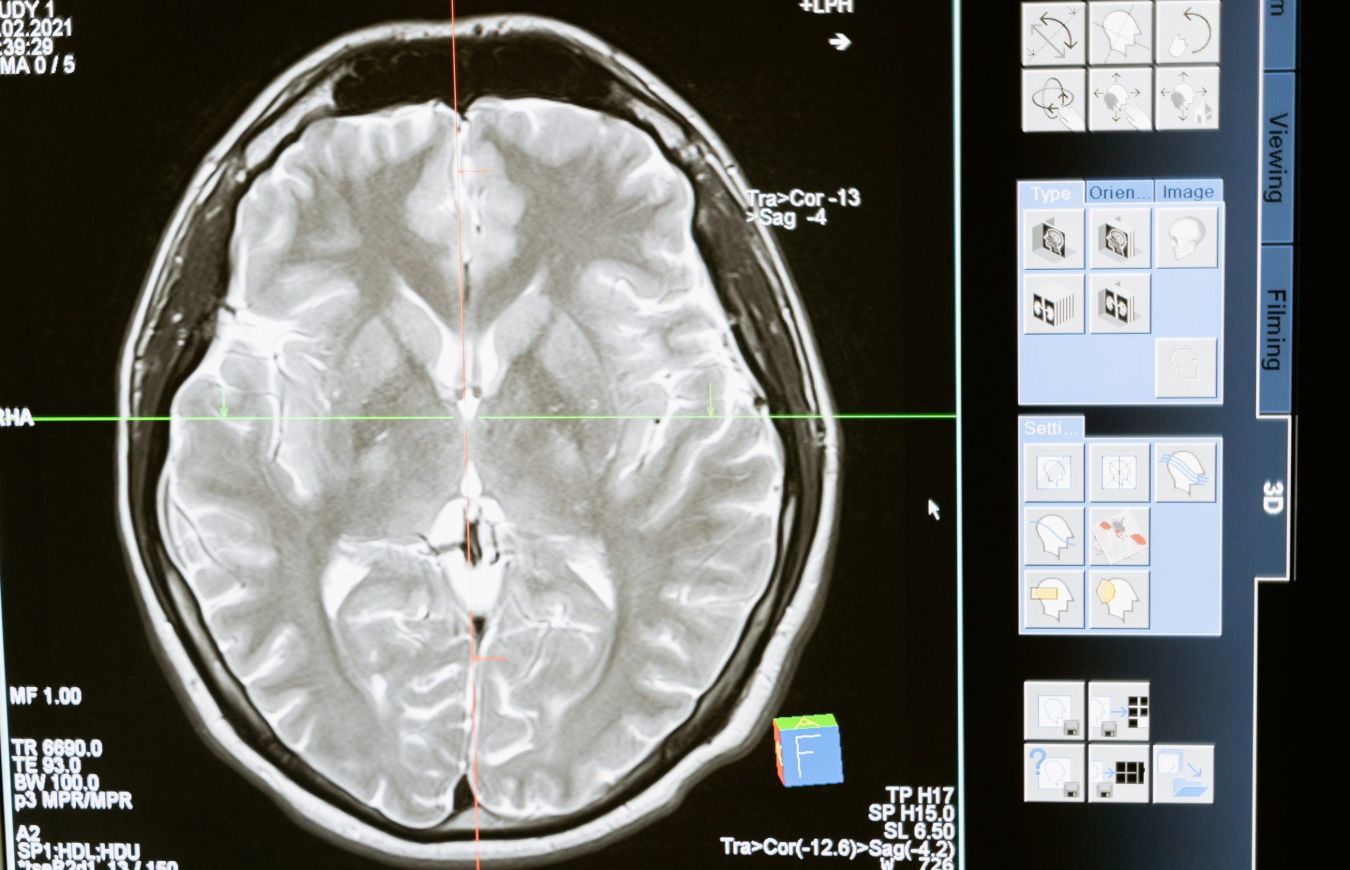

Een urine- of bloedtest om te checken of een hersentumor terugkomt: mogelijk is dat in de toekomst voor patiënten de vervanging van de gebruikelijke driemaandelijkse MRI-scans. Onderzoekers van Amsterdam UMC en de universiteit van Cambridge ontwikkelden twee testen hiervoor. Hun bevindingen zijn vandaag gepubliceerd in het wetenschappelijke blad EMBO Molecular Medicine.

Wanneer bij patiënten een hersentumor is weggehaald, is de kans dat de tumor terugkomt groot. Daarom krijgen ze elke drie maanden een nacontrole met een MRI-scan. De onderzoekers, onder leiding van Florent Moulière, gevestigd in Amsterdam UMC, en Richard Mair van het Cancer Research UK Cambridge Institute, University of Cambridge, ontwikkelden twee verschillende methoden om dit te doen. Moulière: “Hoewel dit onderzoek zich nog in de beginfase bevindt en slechts een klein aantal patiënten is geanalyseerd, zijn de resultaten veelbelovend. In de toekomst kan dit ertoe leiden dat de patiënt thuis een reguliere urinetest afneemt in plaats van een MRI-scan. De test zou een terugkerende kanker eerder en gemakkelijker kunnen opsporen.” Mair vervolgt: “Dit kan artsen ook helpen om de volgende behandelingsstappen te bepalen en de patiëntresultaten te verbeteren.”